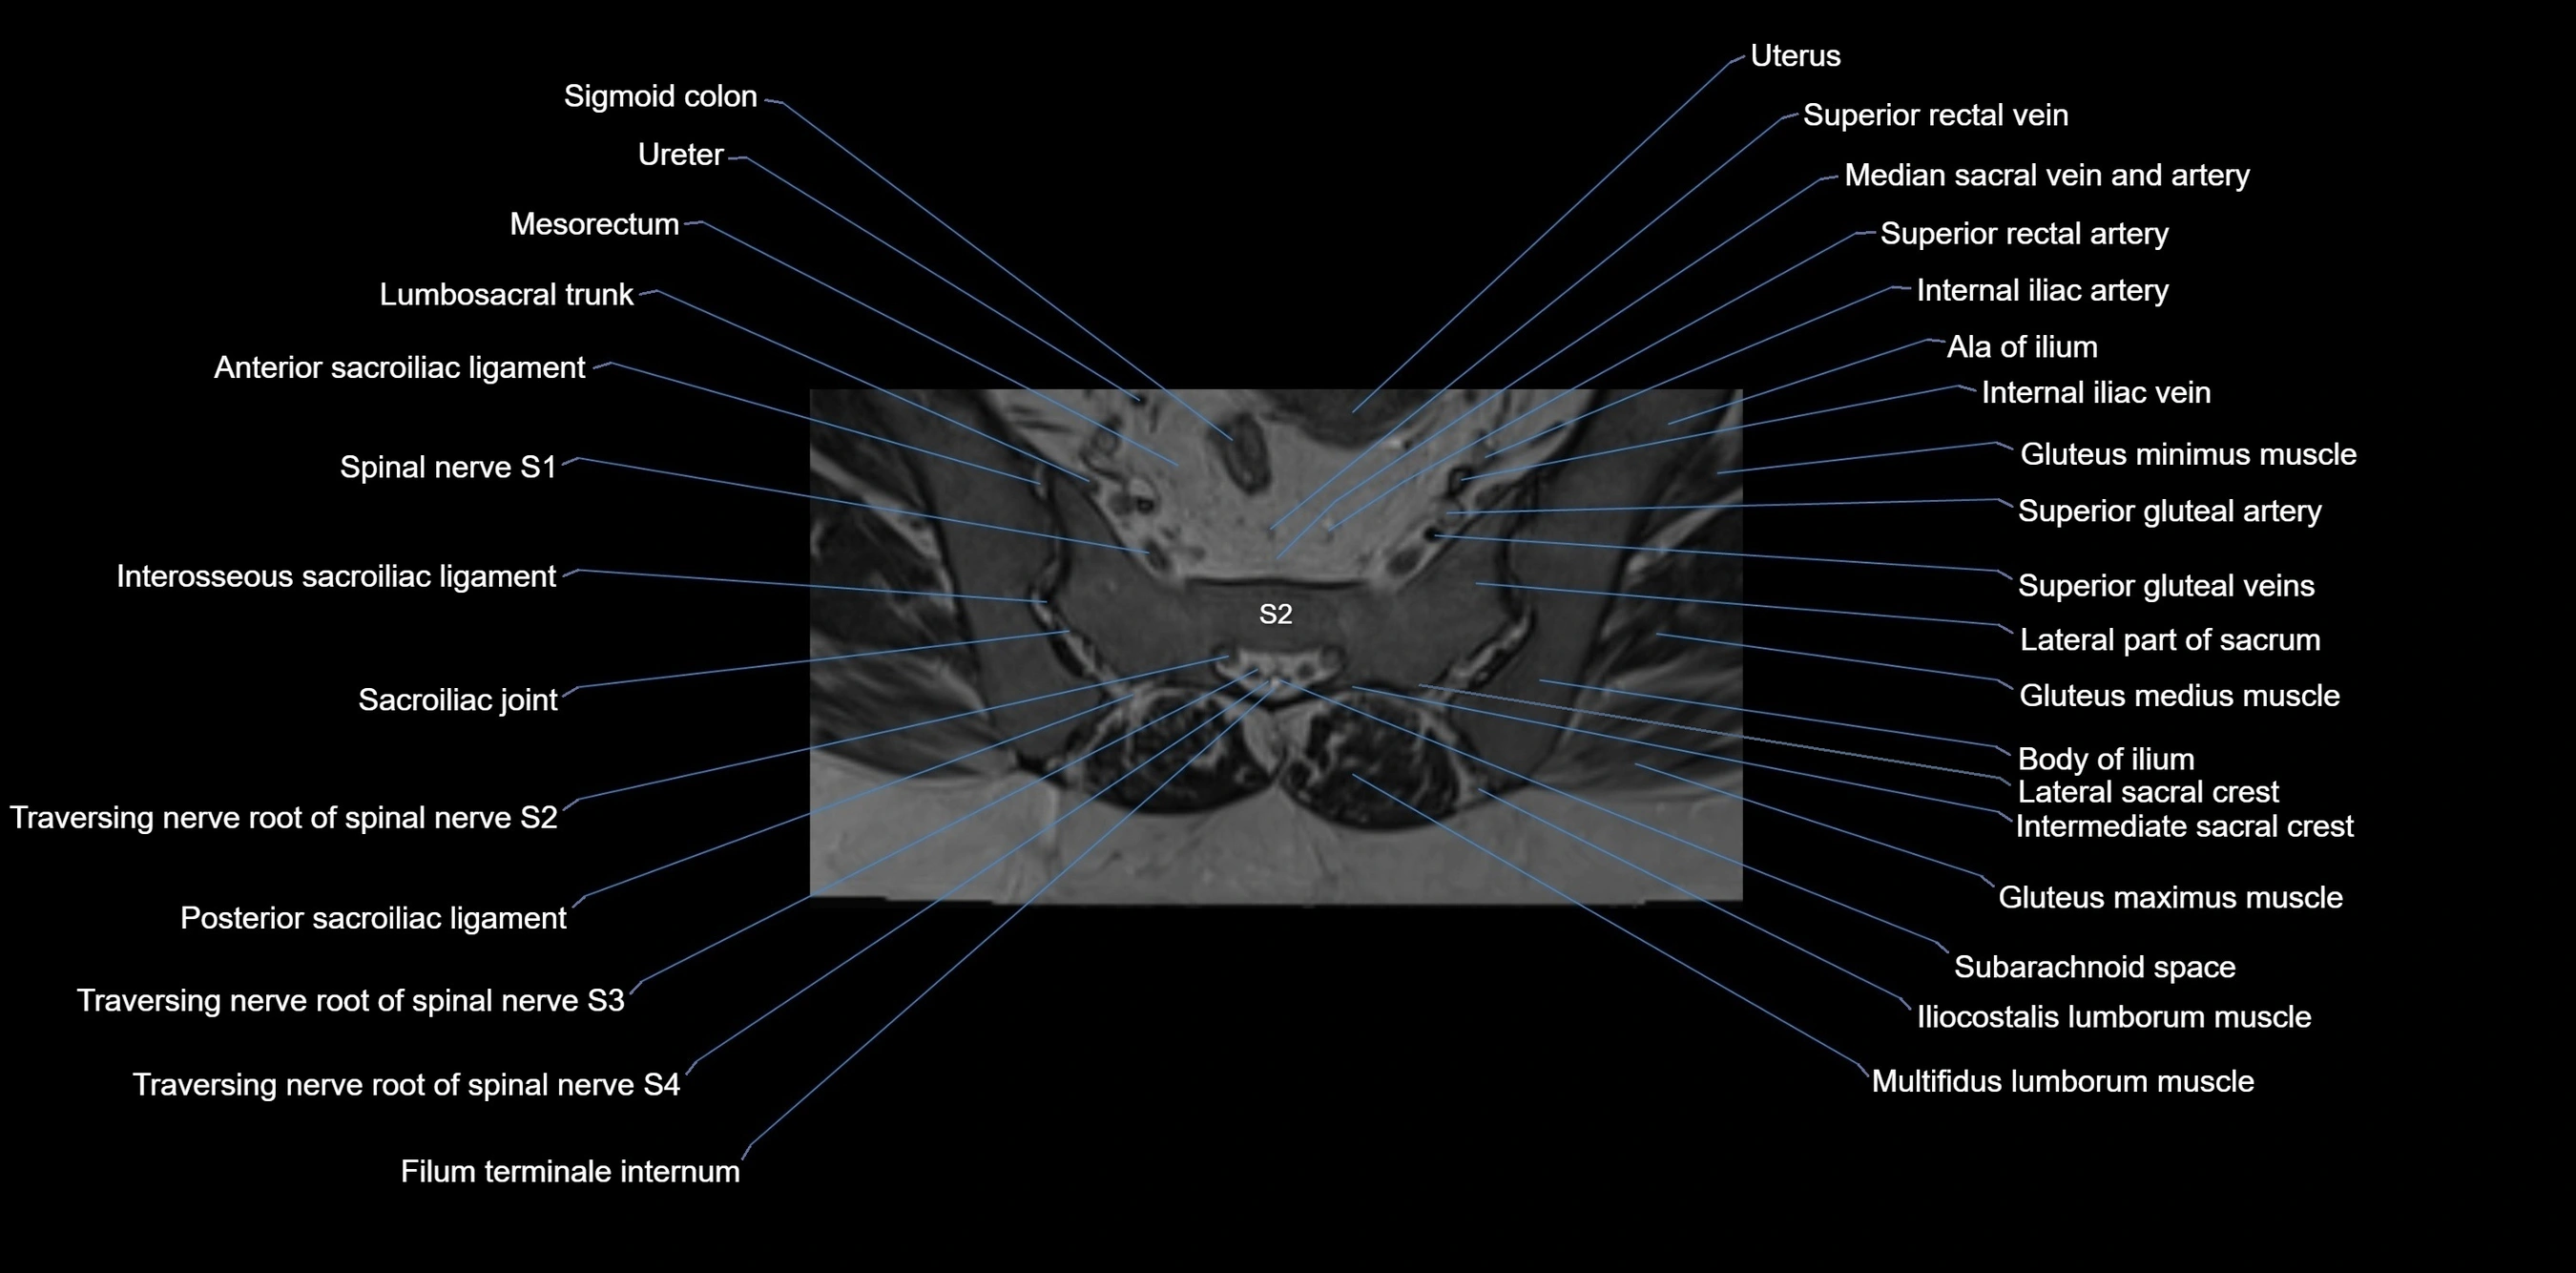

MRI Appearance

T1-weighted images:

• Cortical bone appears very low signal (dark); marrow shows intermediate signal

• Iliac fossa fat is bright against low-signal cortex

T2-weighted images:

• Cortical bone remains dark

• Marrow signal varies depending on fat content; edema or tumor shows hyperintensity

STIR:

• Suppresses fat, making bone marrow edema, fractures, or infiltrative lesions appear bright

• Excellent for trauma, sacroiliitis, and metastatic evaluation

T1 Fat-Saturated (Pre-contrast):

• Marrow: intermediate signal, fat suppressed

• Useful for detecting subtle marrow abnormalities adjacent to iliac cortex

T1 Fat-Saturated Post-Contrast (Gadolinium):

• Enhances vascularized structures, marrow pathology, tumors, and inflammatory changes

• Highlights soft tissue or bone invasion in pelvic neoplasms

MRI Non-Contrast 3D Imaging:

• Provides 3D morphology of iliac wing, crest, and articulations

• Used in preoperative planning for pelvic surgery and trauma reconstruction

MRI image

image